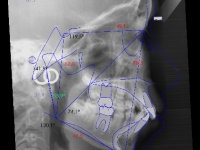

El paciente D.M. llega a nuestra consulta sin los 2 premolares inferiores que le quitaron en anteriormente para empezar a mejorar el caso.

– Perfil plano

– Clase III esquelética

– Clase III dental

– Apiñamiento superior muy importante

Fotos antes de tratamiento: